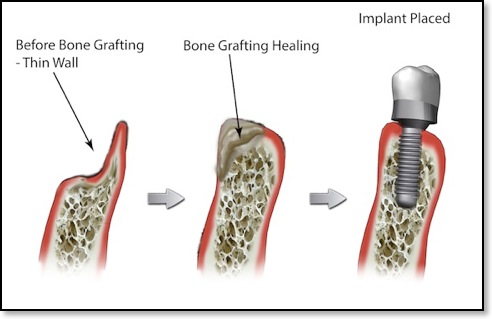

The other common type of bone graft for dental implants is a Ridge Augmentation, Ridge Enhancement, or Split Ridge. (See the diagram above.) Sometimes, when a patient has lost their tooth many months or years ago, the bone in that area has resorbed (the bone is lost). The remaining bone is too thin to support the dental implant. In such cases, Dr. Tsai would numb the area where the thin wall is, gently pull the gum tissue back, pack or place the bone graft in place, and suture the gum back into place. Sometimes Dr. Tsai will “split” the ridge and pack in the bone graft in order to thicken up the bone for the implant. This procedure typically takes 4-7 months to heal. Once the bone grafting has integrated or is healed, the dental implant can be placed.